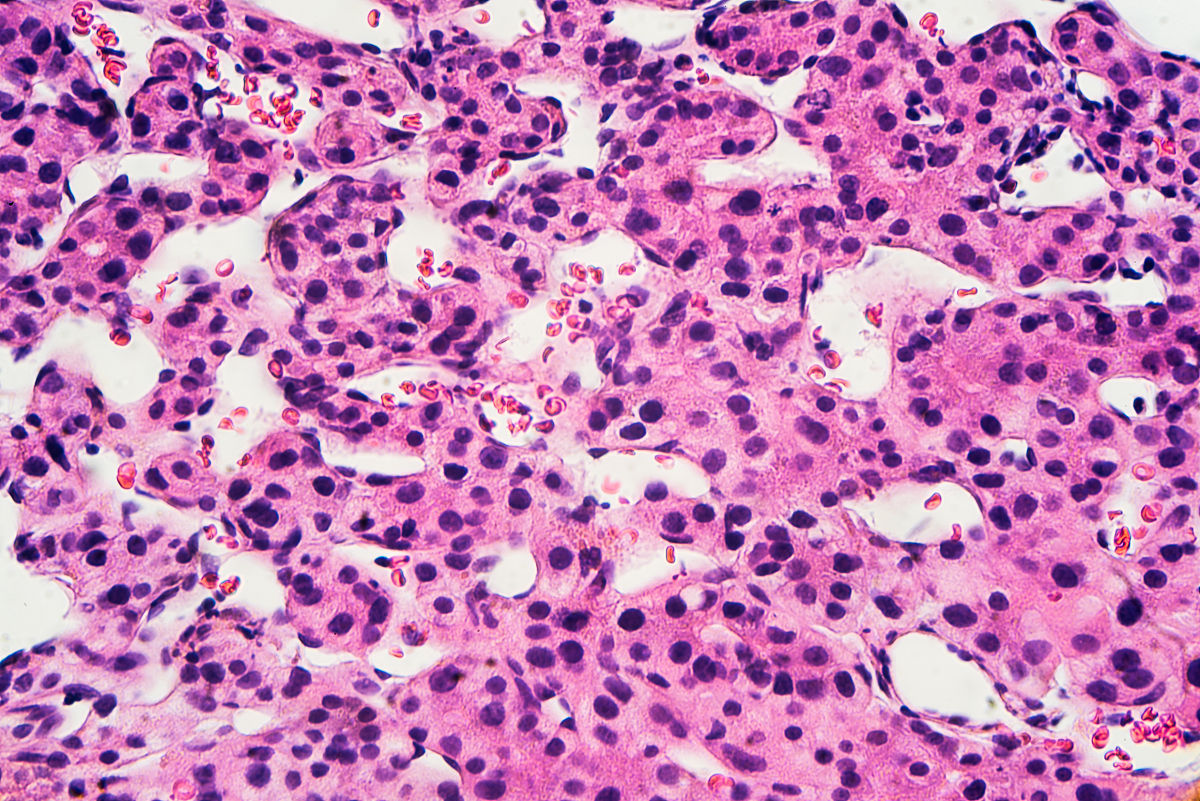

病理学检查:肝癌为恶性肿瘤,病理学检查可见肿瘤细胞的浸润和破坏周围正常肝组织,可见细胞异型性、核分裂象等恶性肿瘤的特征。而肝血管瘤为良性肿瘤,病理学检查可见肝血管壁增厚,血管内充盈血液,无肿瘤细胞浸润和病变征象。